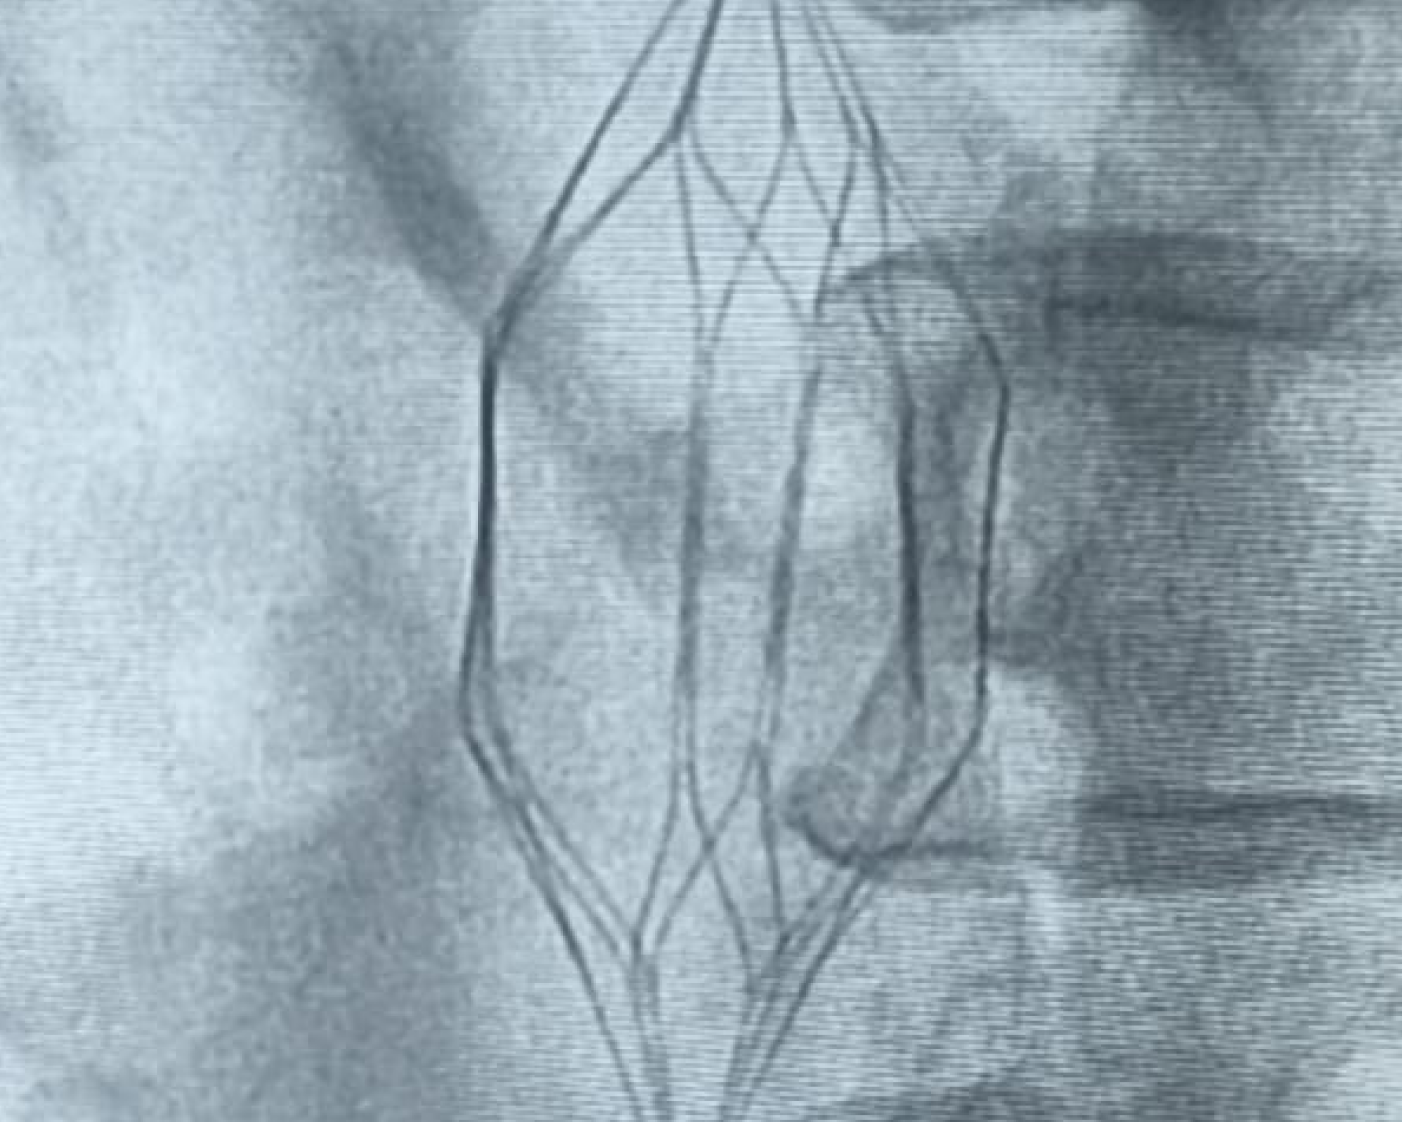

Interventions including Angiograms, Pacemaker Implantation, and Coronary Stenting.

Advanced pacemaker procedures with precise placement and monitoring to improve heart rhythm and recovery.

Advanced ICD implantation to manage dangerous heart rhythms with precision and monitoring for better outcomes.

Advanced CRT implantation to improve heart coordination with precision and monitoring for better outcomes.

Pacemakers